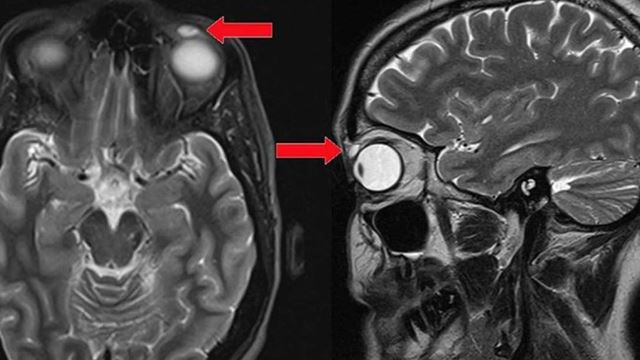

Mata Kena Smash Dengan Bulu Tangkis, Contact Lens Ada Belakang Mata